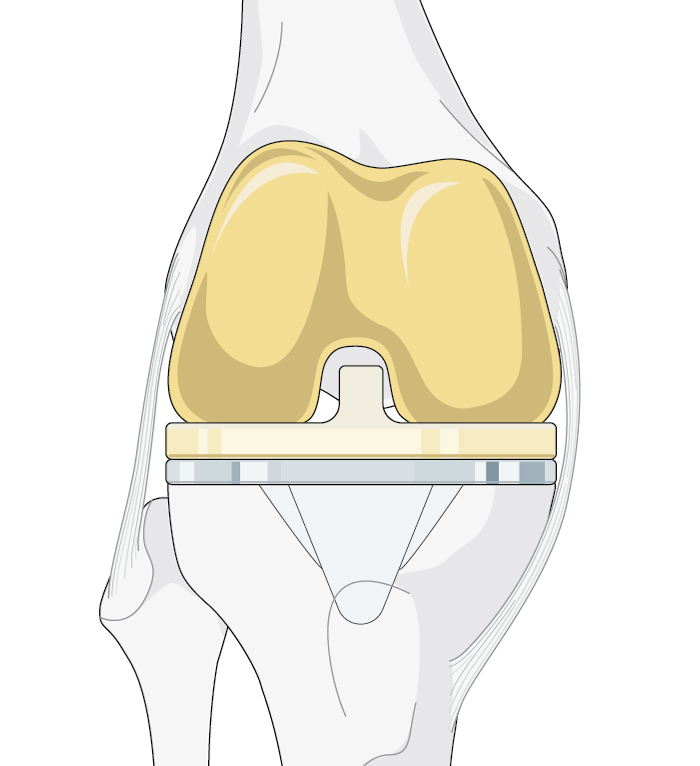

Figure 1. TKA, HTO, and UKA are all viable options to address osteoarthritis of the knee. However, there are situations that indicate the selection of one over the others.